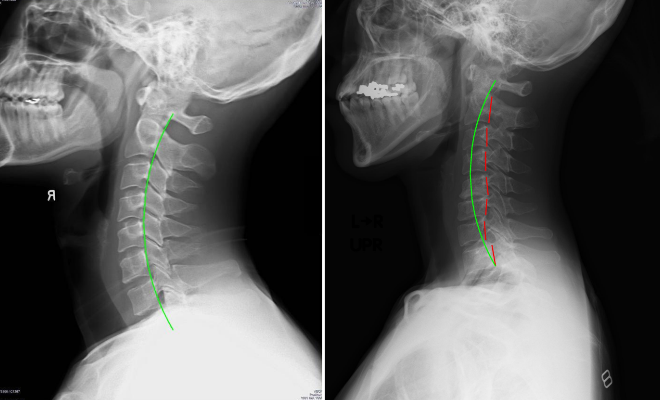

【実際の写真】

解説:左写真が理想的なライン。右写真の赤い部分から、ストレートネックであることが分かる

CBPによるレントゲン分析は、理想的な骨の位置からのズレを数字で見られるのが特徴です。

「歪んでいるね」などの漠然とした診断ではなく、エビデンスに基づいた診断。

患者の立場としても納得できるものでした。